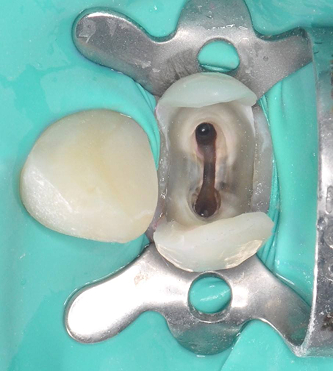

Лечение: Проведено перелечивание корневых каналов под микроскопом с удалением ранее внесённых материалов, тщательной механической и медикаментозной обработкой каналов и их последующей герметичной обтурацией. После лечения каналов выполнено восстановление коронковой части зуба.